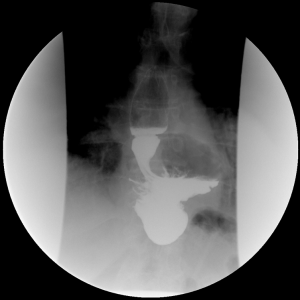

Laparoscopic primary fundoplication is now a well-established treatment for gastroesophageal reflux disease (GERD) (1), with failure rates ranging from 2% to 30% (2-7). The most common cause of failure of the primary fundoplication is transmediastinal migration of the wrap or recurrence of hiatal hernia (8) (Figure 1). Factors contributing to recurrence include failure to identify a short esophagus, inadequate crural closure, and improperly placed fundoplication (1,8). Most patients who present with symptoms of recurrent reflux after a fundoplication can be managed non-operatively with optimal medical therapy, endoscopic treatment, and lifestyle modification. However, 3% to 6% of patients with intractable GERD symptoms following primary fundoplication may benefit from re-operative surgical intervention (9). The surgical options for failed primary fundoplication for esophageal preservation include redo-fundoplication with or without an esophageal lengthening procedure, and Roux-en-Y near esophagojejunostomy (RNYNEJ). In select instances esophagectomy may be the only viable option.